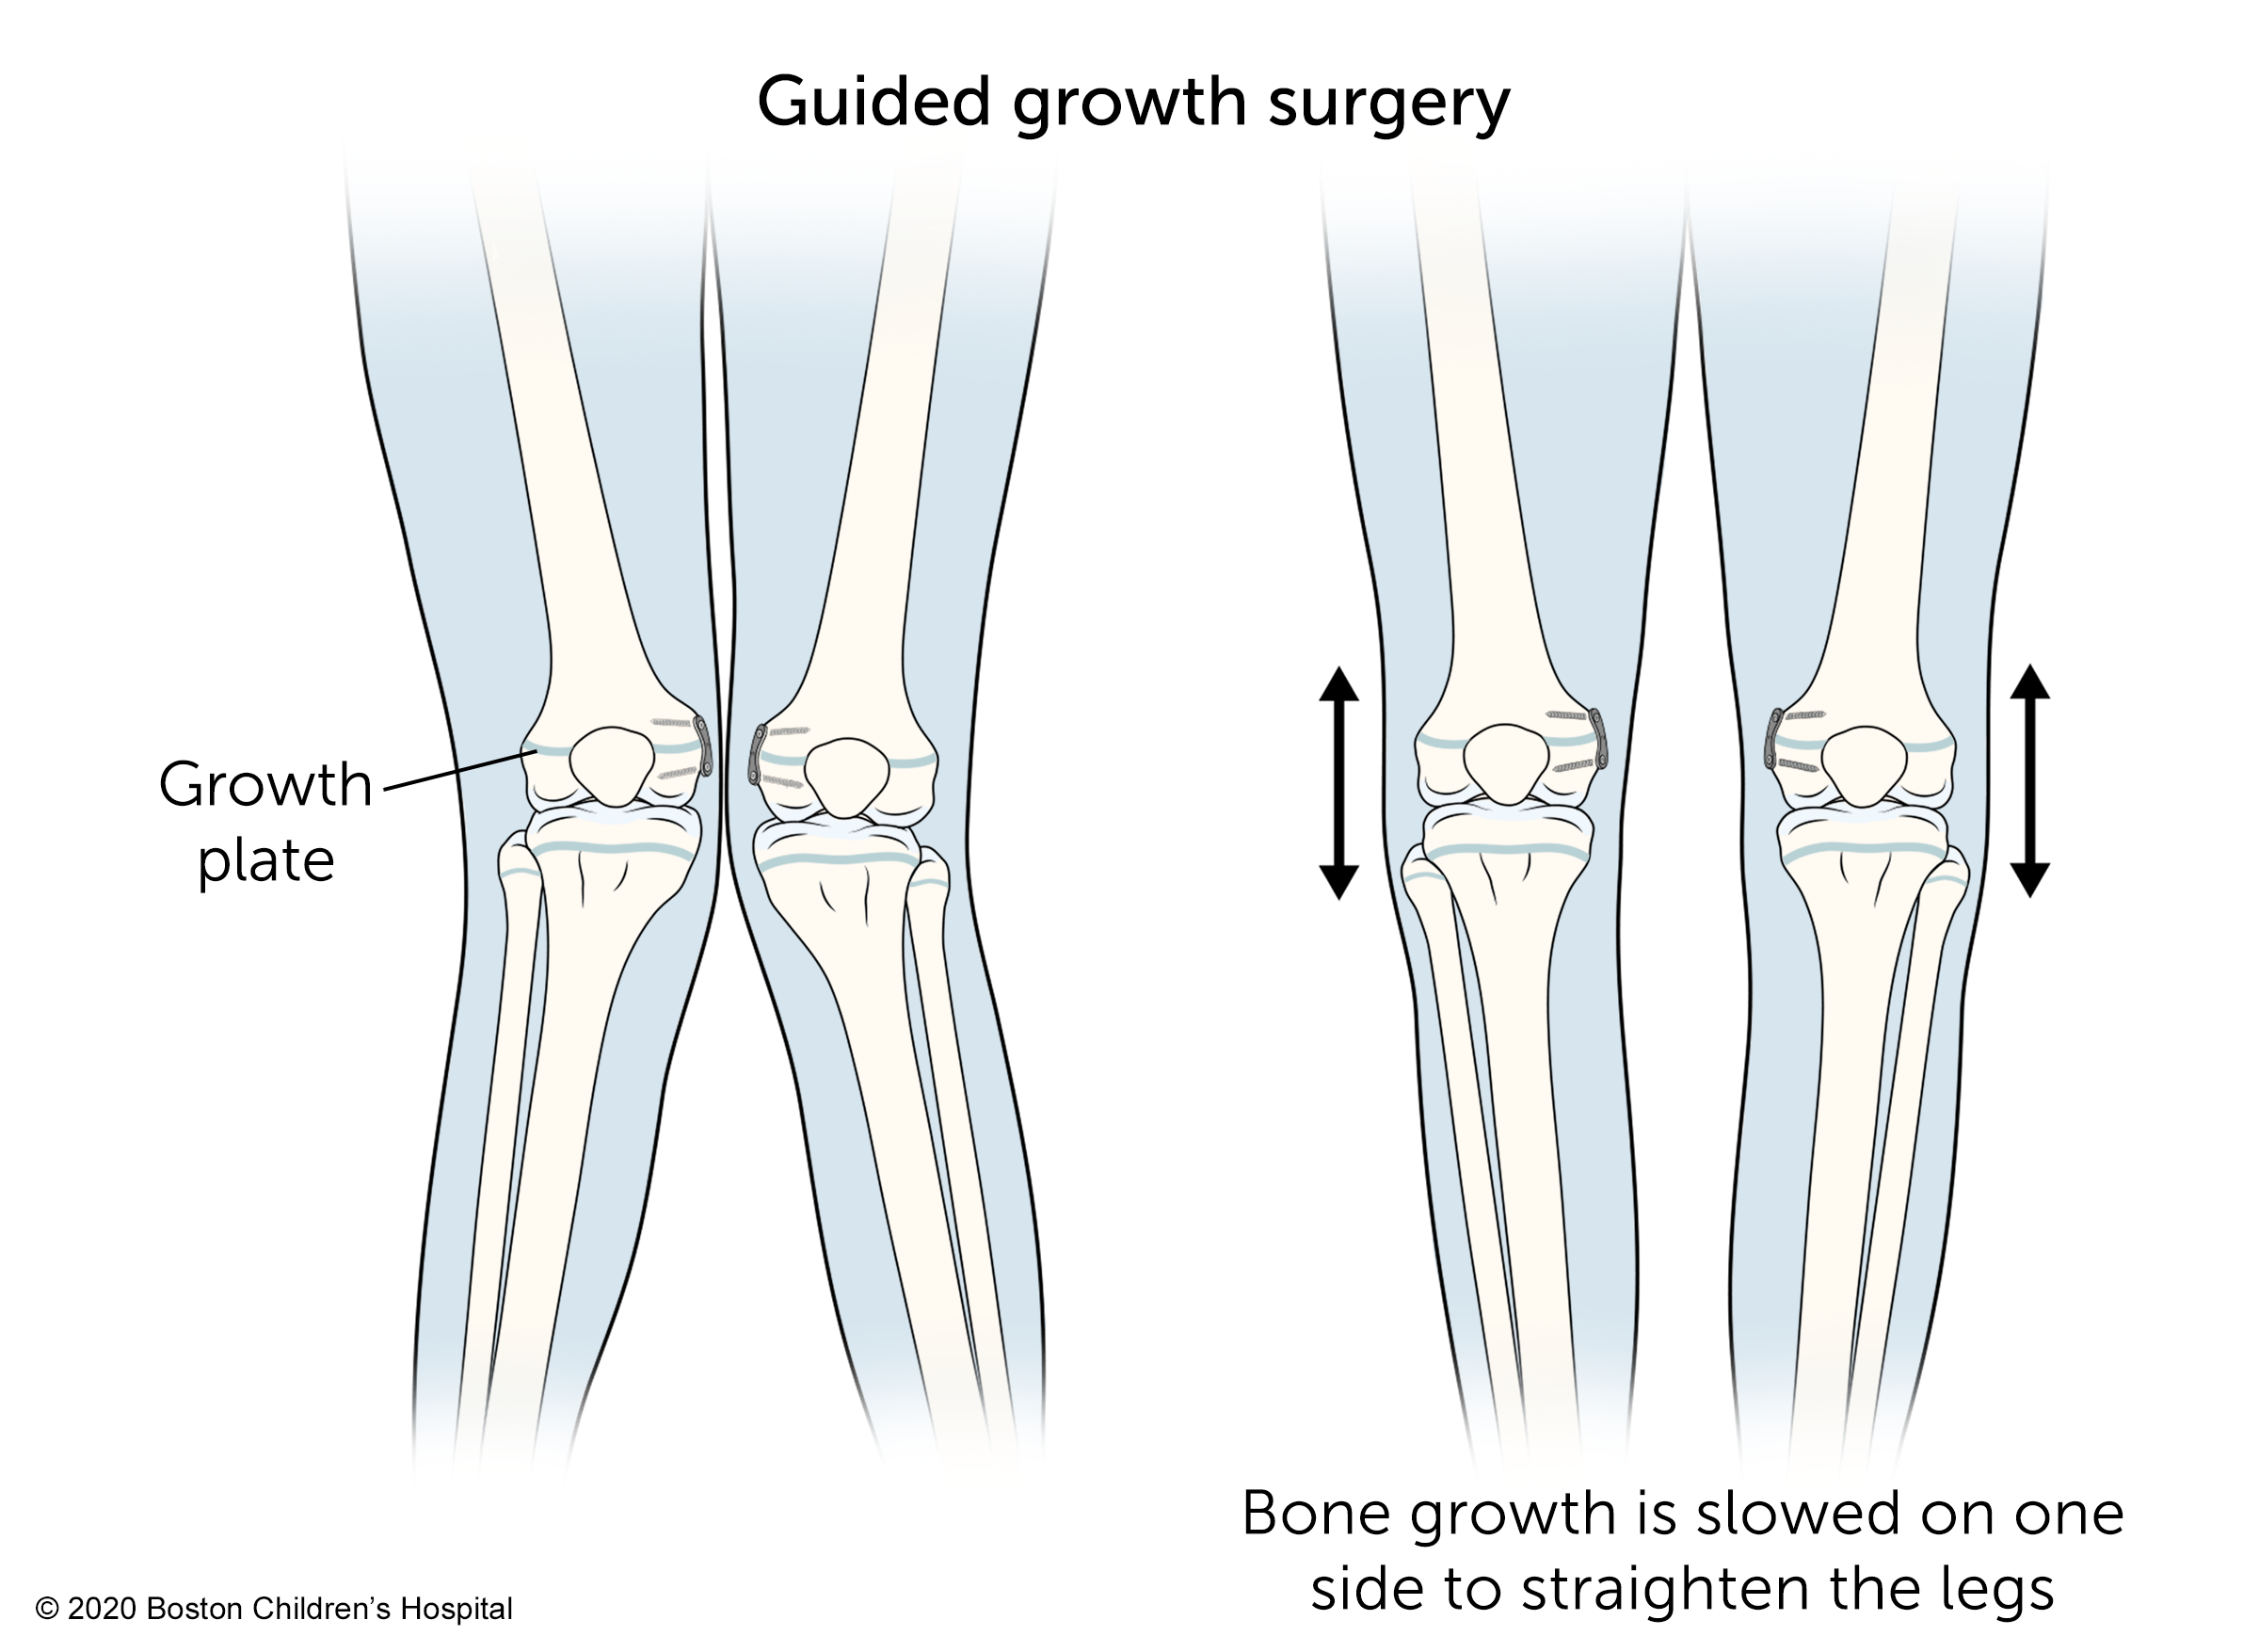

Guided growth surgery

Guided growth surgery corrects knock knees by slowing the growth on the bent side of the bone so the other side can catch up. The surgeon implants small metal devices on the inner side of the growth plates around the knees. The outer side of the knees will continue to grow, causing the legs to grow straighter.

Children usually have guided growth surgery when they're approaching puberty, before their adolescent growth spurt. This is usually around age 11 for girls and 13 for boys.

Guided growth surgery is an outpatient procedure. Children can bear weight on their legs immediately and return to activity within a few weeks after the procedure.